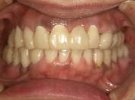

54歳女性

部分義歯がどうしても違和感が強くて、できれば義歯を使わなくてもいいようにしたいとのこと。

下顎はそんなに問題ないですが、上顎は骨の厚みと量、共に乏しく本来はインプラントは不可能です。

あきらめずに、かなり高度な技術ですが骨を増やす手術を併用してなんとか植えることができました。

術前

↓↓↓↓

術後